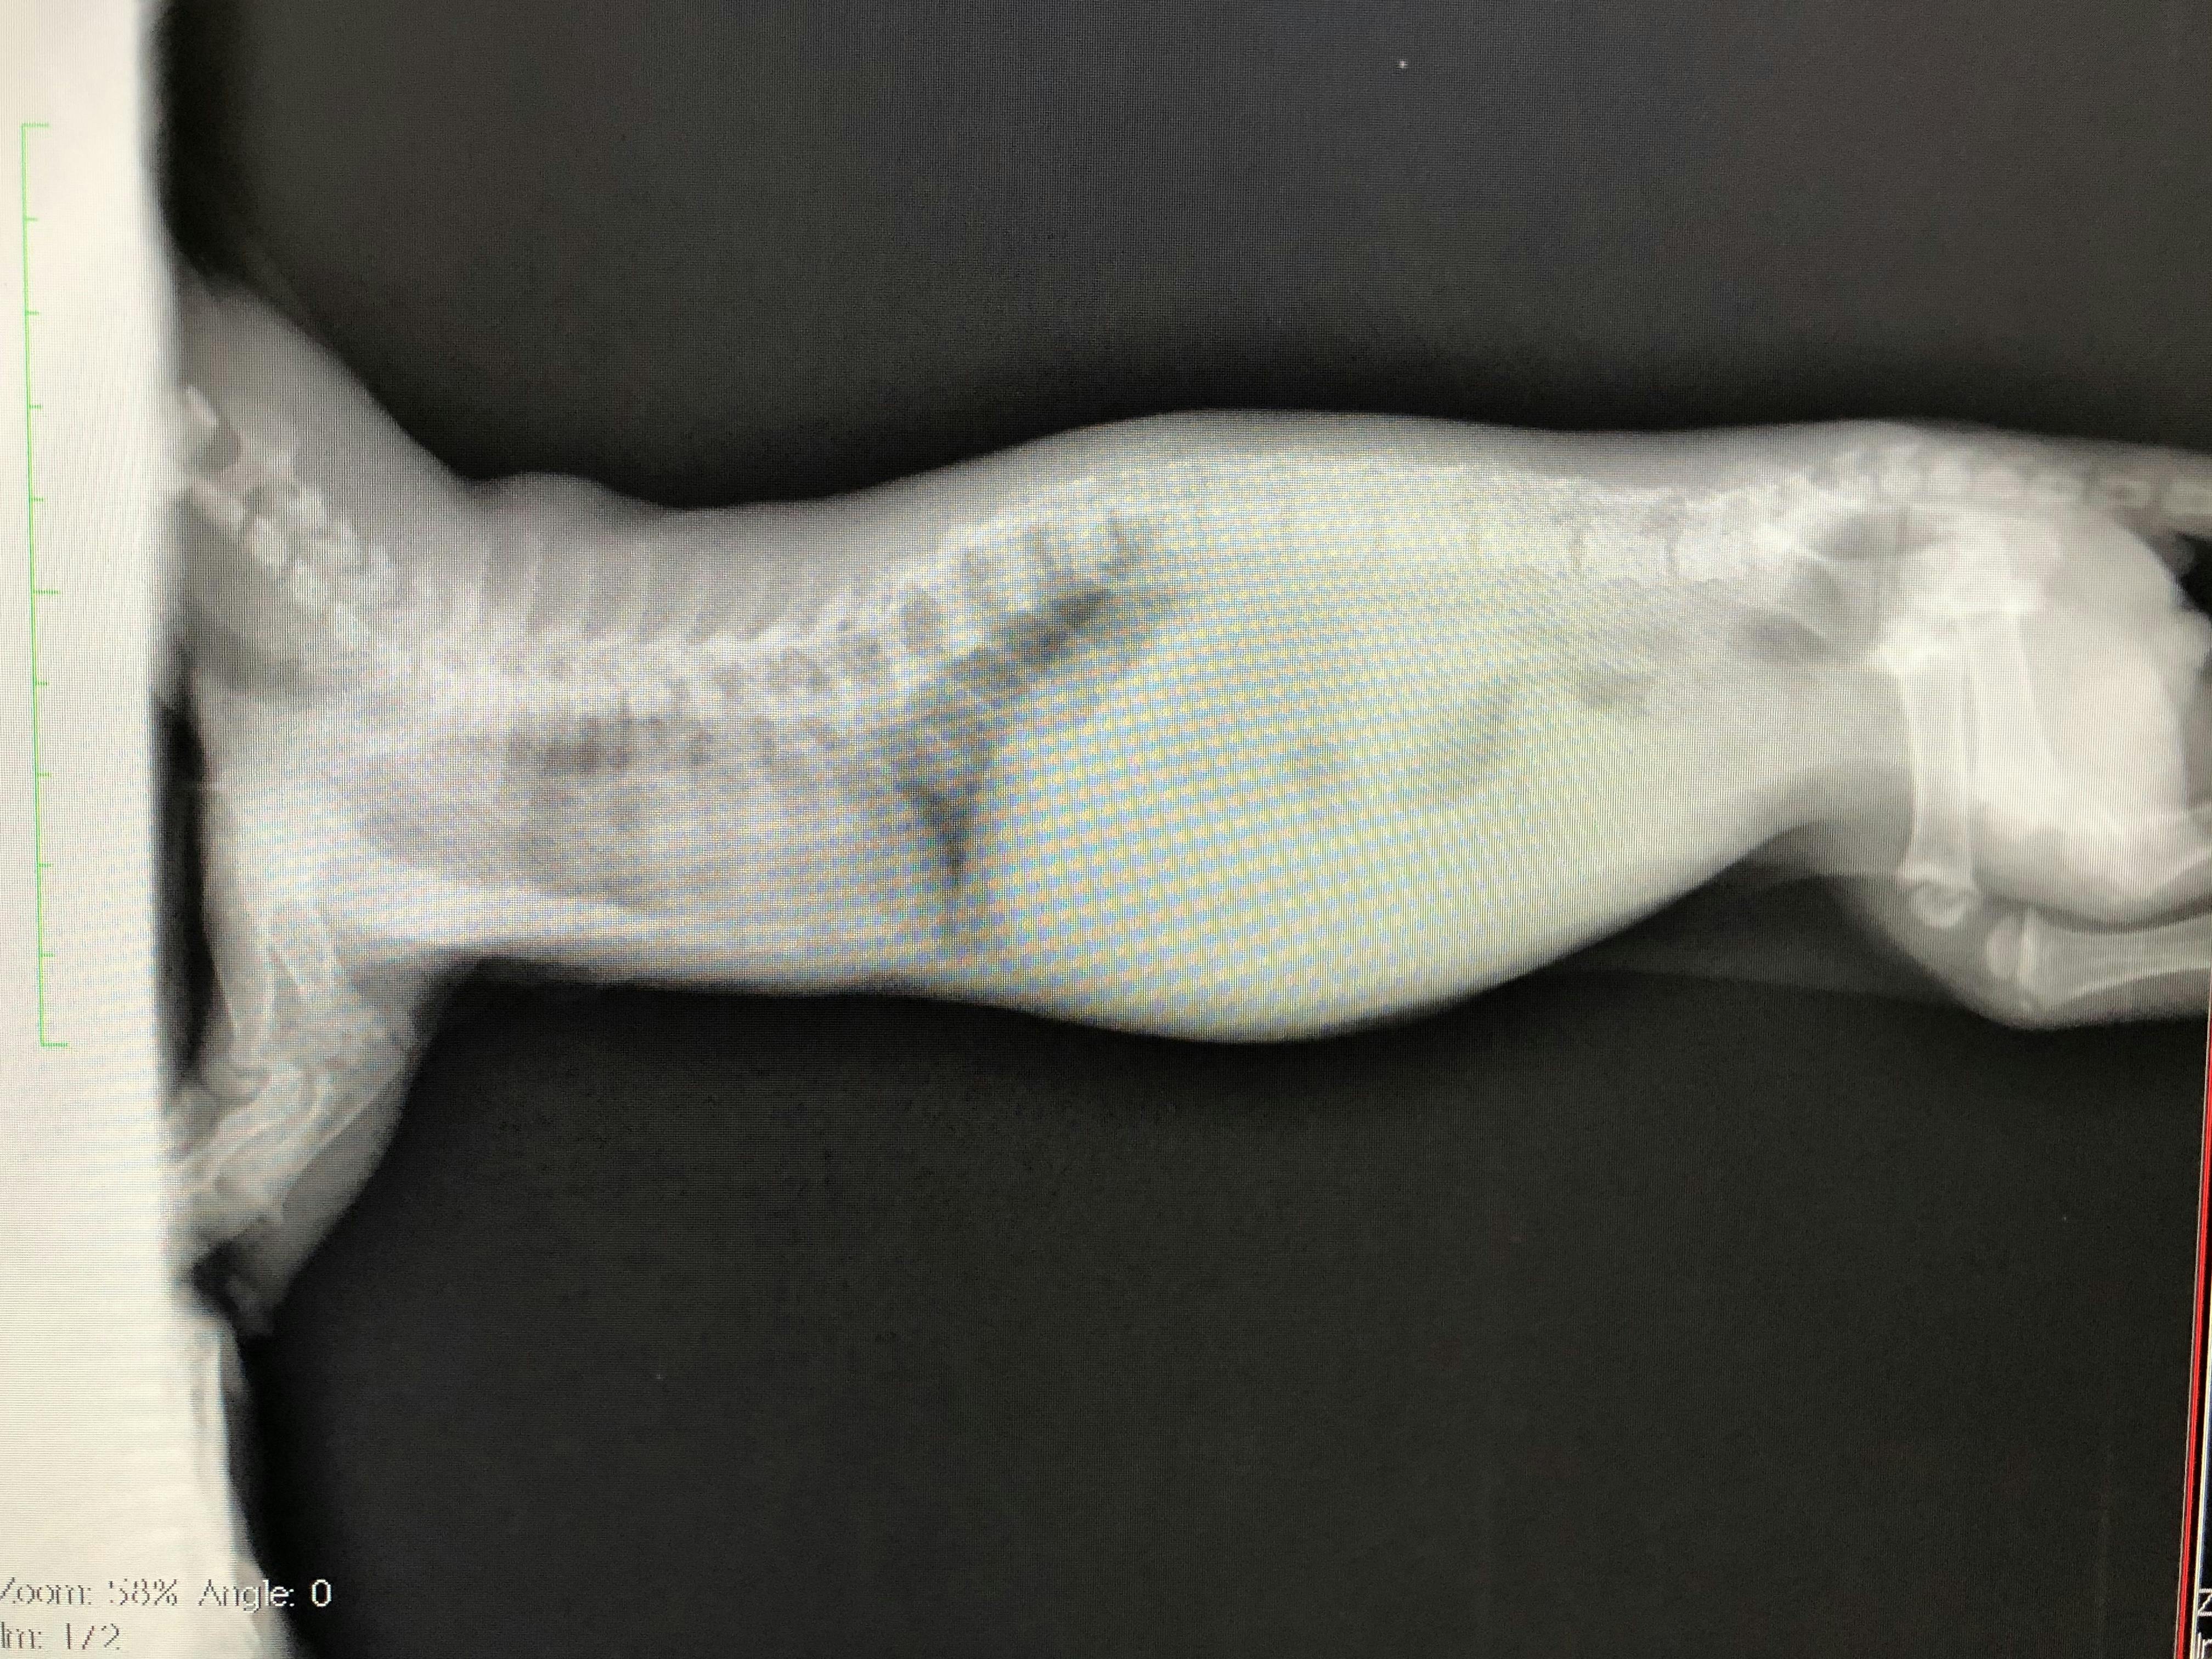

肋骨変形に伴う脊椎側変症

先天的な骨格異常で背骨と肋骨が変形していると診断されました。

また、この骨格異常により、肋骨と背骨の間のスペースが狭く、このまま成長していくと心臓と肺が圧迫され最悪生きられないと言われました。

検査費

レントゲン、CT撮影で費用が嵩む上、成長過程のため、複数回必要とのこと。これらを総合し、合計150万円〜は用意しておいて下さいと言われました。